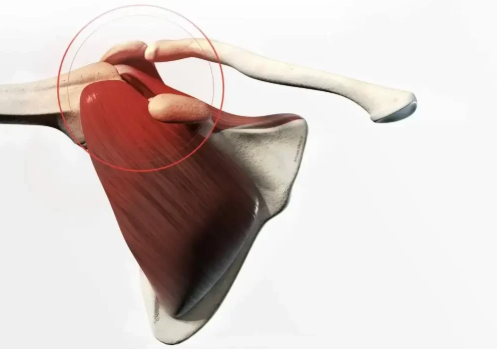

Les gestes répétitifs ou l’usure naturelle peuvent provoquer une rupture des tendons de la coiffe des rotateurs, essentiels au bon mouvement de l’épaule. La chirurgie de l’épaule permet de restaurer ces tendons et de rétablir une mobilité optimale.